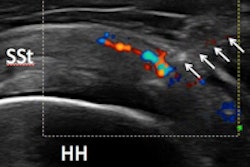

With PRP therapy, blood is collected from patients and spun in a centrifuge to separate the PRP from other blood components. The PRP is then injected under ultrasound guidance into the target area to stimulate cellular growth and healing.